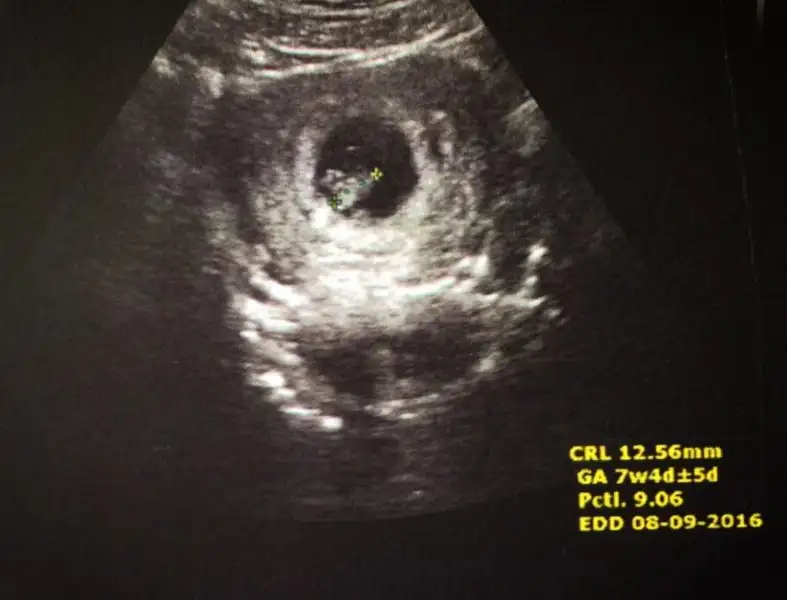

Buda ablasının özlemle bekleyip sonunda kavuştuğu kardeşi :KK37:

• 1453987768160-210884203.webp

1453987768160-210884203.webp

12,2 KB · Görüntüleme: 119